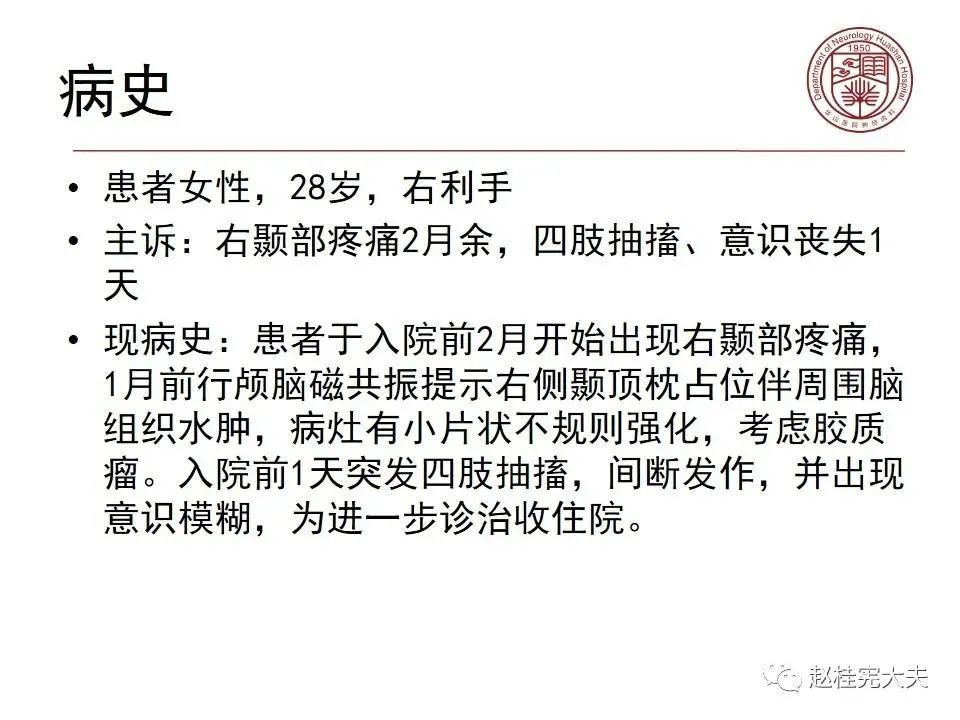

病例3